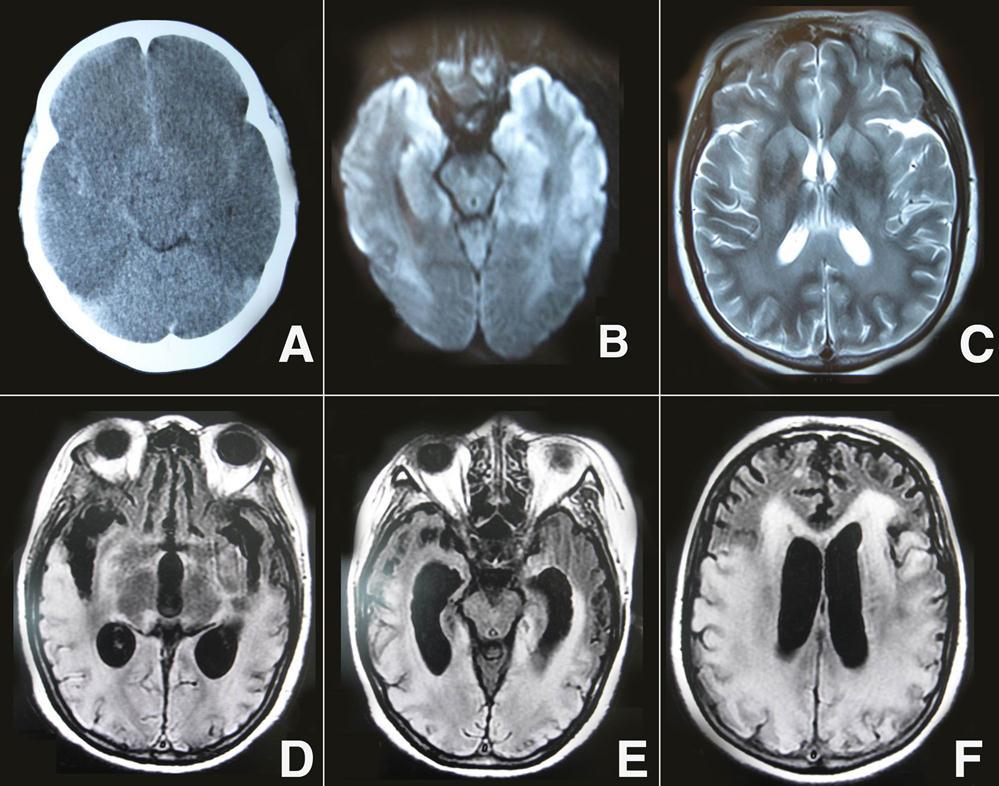

A 46-year-old woman was found in cardiorespiratory arrest after she had an out-of-hospital an suddenly drop atroke lasting about 27 min. She was successfully resuscitated and admitted to the intensive care unit.The etiopathogenesis of cardiac arrest was ventricular fibrillation for patient. On initial examination, her pupils were 2 mm in diameter and nonreactive to light, and there was unresponse to external stimulation, and the score on the Glasgow Coma Scale was 3(E1V1M1). On admition, initial head CT revealed no significant findings. On the three days after onset, a repeat noncontrast CT images showed a whole cerebral brain swelling, caudal transtentorial Herniation, and microhemorrhages in the intercerebral and subarachnoid (Figure 1A). Diffusion- weighted magnetic resonance imaging (DWI) performed on day 14, the patient showed extensive lesions of the bilateral middle, hippocampus and the gray matter of the frontal and temporal cortices (Figure 1 B). In addition, brain MRI T2-weighted imaging showed bilateral symmetric high signal intensity in the caudate, putamen, thalami, occipital, parietal cortices and subcortical white matter (Figure 1C). After 20 days, her neurological status was improved, the GCS scale was 8 (E4V1M3). she did not show any signs of conscious perception regarding the different types of stimulation, including pain. She had been in a vegetative state. On follow-up MRI 60 days later, Fluid-attenuation inversion recovery image (FLAIR) showed cortical, subcortical white matter, and periventricular white matter confluent hyperintense lesions in the bilateral temporal, parietal, and occipital regions, and enlarged ventricles (Figure 1D-F). After three months, she did not perform requested commands and displayed spastic palsy to a higher extent in the lower limbs. The GCS scale was 9 (E4V1M4), and she was declared a persistent vegetative state.

Figure 1.A) Brain CT showed a whole cerebral brain swelling, caudal transtentorial Herniation, and microhemorrhages in the intercerebral and subarachnoid; B) DWI showed extensive lesions of the bilateral middle, hippocampus and the gray matter of the frontal and temporal cortices; C) brain MRI T 2-weighted imaging showed bilateral symmetric high signal intensity in the caudate, putamen, thalami, occipital, parietal cortices and subcortical white matter; D-F) On follow-up MRI 60 days later, FLAIR showed cortical, subcortical white matter, and periventricular white matter confluent hyperintense lesions in the bilateral temporal, parietal, and occipital regions, and enlarged ventricles.

Post-Resuscitation Encephalopathy (PRE), is a relatively frequent condition. PRE is introduced as a term to describe the comatose state after CPR.1 The prognosis of CPR is different, depending on whether the brain damage is reversible or irreversible. Our patient was confirmed that early CT scan of CPR may not have abnormal changes, and upon to the 2-3 days later she had obvious diffuse edema and minor intercerebral hemorrhages. Therefore, the monitoring of the diffuse edema and mimic minor hemorrhages on brain CT is useful for an early diagnosis of PRE. However, most studies have confirmed that MRI is more useful for predicting prognosis than CT scan. On the day 14 after onset, DWI showed extensive lesions of the bilateral middle, hippocampus, caudate, putamen, thalami, occipital, parietal and the gray matter of the frontal and temporal cortices. Previous studies indicated that presence of a lesion pattern of multilobar, or diffuse, cortical involvement, termed as "extensive cortical lesion pattern", and associated with poor outcome. 2, 3 In fact, on the 20 days of onset, the patient'neurological status was improved, and her GCS scale was 8 (E4V1M3). Moreover, on follow-up MRI 60 days later, the hyperintense lesions in the bilateral frontal, thalami, and middle have been reversed,suggesting some cortical and subcortical cerebral lesions were reversible. However, periventricular white matter confluent hyperintense lesions in the bilateral temporal, parietal, and occipital regions have not been reversed, suggesting these hyperintense lesions were irreversible. An earlier study has showed that patients with bilateral basal ganglia, thalami, and/or substantia nigra lesions may survive in a persistent vegetative state (PVS).4 Current MRI-FLAIR found that patients with bilateral temporal, parietal, and occipital extensive lesions may also survive in a PVS.